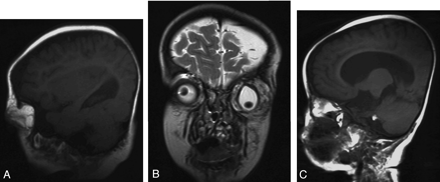

A multilobulated circumferential peribulbar intraorbital mass with supraorbital extension was observed on MR imaging with a signal intensity similar to that of subcutaneous fat on all pulse sequences. The eyeball had a bizarre shape with an inferiorly dislocated lens (Fig 1A, -B). Ipsilaterally, there was a lipoma in the cerebellopontine angle cistern, and the subcutaneous fat over the left frontotemporoparietal region was diffusely thicker than that of the right side (Figs 1C and 2C). Left cerebral hemiatrophy was present with dilated lateral ventricle and hemispheric sulci. There was a wide cortical developmental malformation over the left temporo-occipital area (Fig 2A–C).

Sagittal T1-weighted spin-echo (TR/TE, 400/9.1 ms) (A) and coronal T2-weighted TSE (TR/TE, 3500/100 ms) images show lipomatous coloboma of the left eye (B). On the sagittal T1-weighted spin-echo (TR/TE, 400/9.1 ms) image of the medial brain, a cerebellopontine angle cistern lipoma is seen (C).

A, Left cerebral hemiatrophy with cortical developmental malformation is seen on the transverse T2-weighted TSE (TR/TE, 3500/100 ms) image. Thin caliber of the left ICA is also observed.

B, T2-weighted TSE (TR/TE, 3500/100 ms) transverse image from a higher section shows the collaterals in the basal cisterns.

C, Coronal T2-weighted TSE (TR/TE; 3500/100 ms) image shows atrophy of the left cerebral hemisphere with dilated lateral ventricles and temporal cortical dysplasia. Also, subcutaneous fat is diffusely thicker over the left frontotemporoparietal cranium.